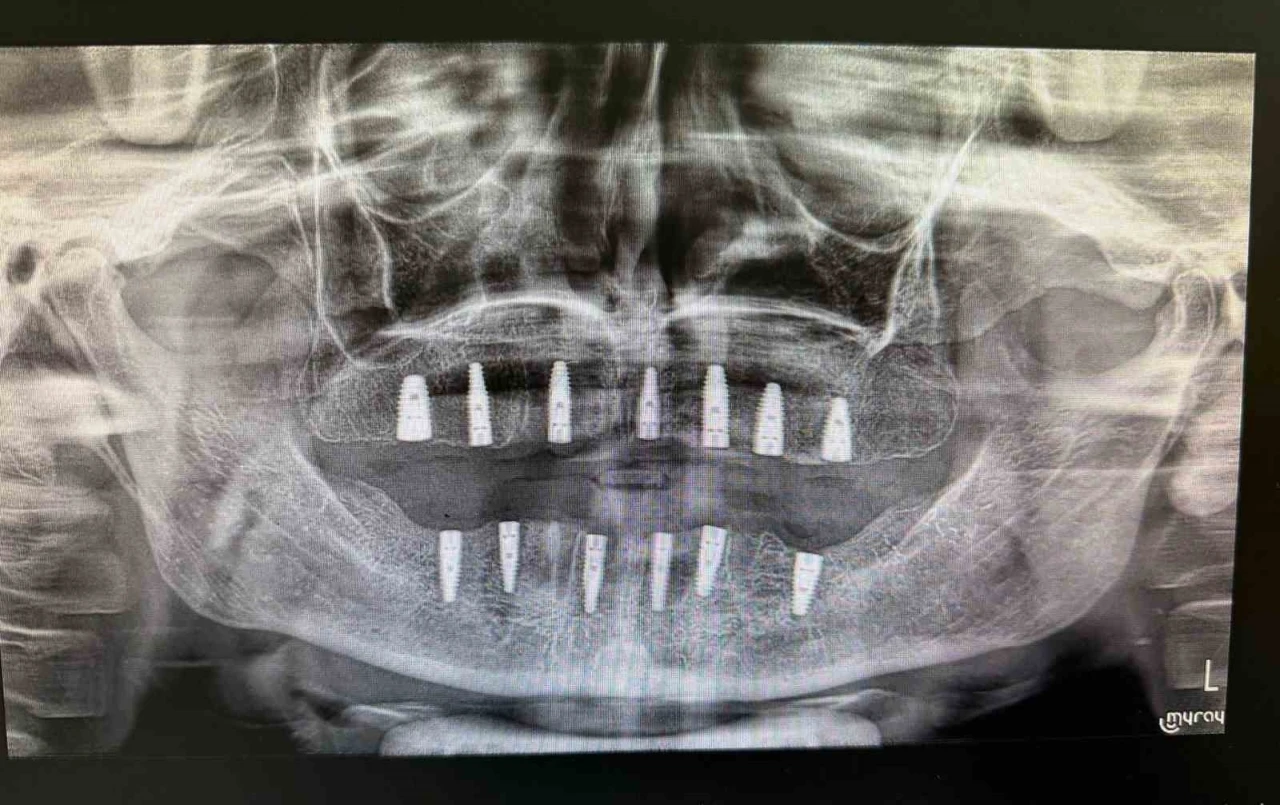

Merkezde görevli Uzm. Dt. Sefa Merve Arıkan tarafından gerçekleştirilen ameliyatta hastaya 13 adet implant yerleştirildi.